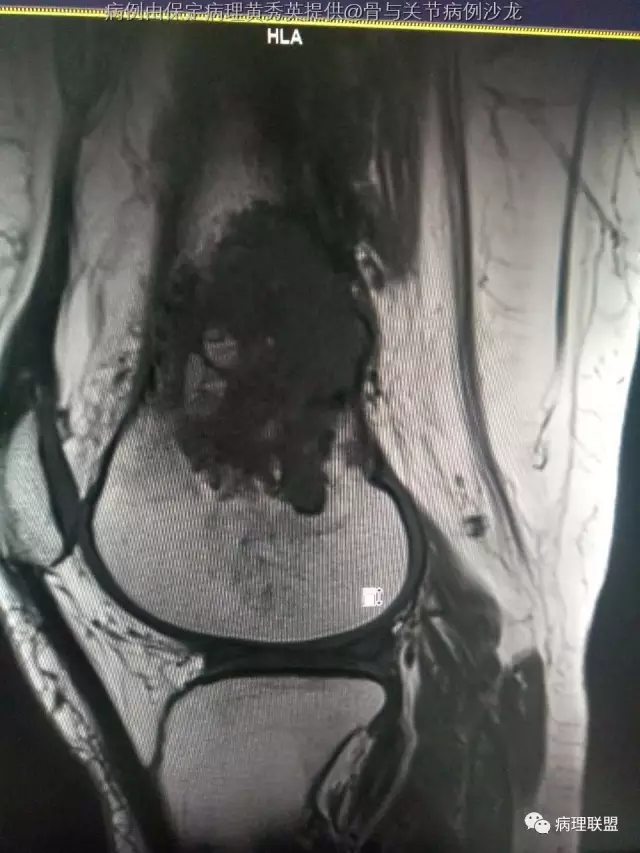

女67岁,股骨下端肿物约6cm,(病例由保定病理黄秀英提供,致谢!)